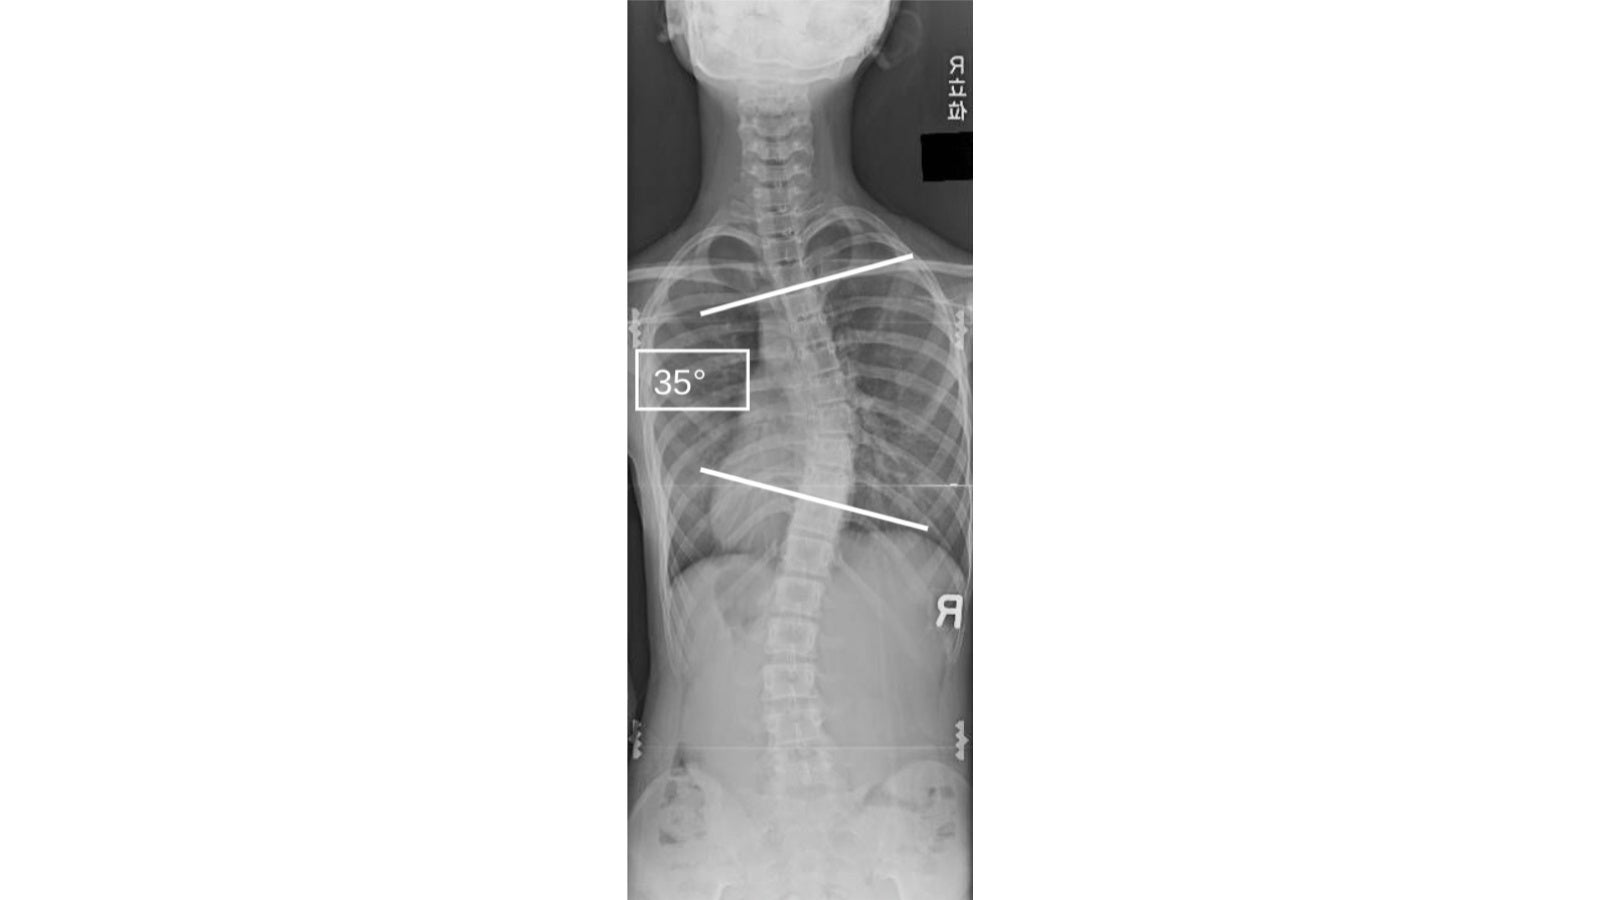

全脊椎の作用と性質

全脊椎の作用と性質